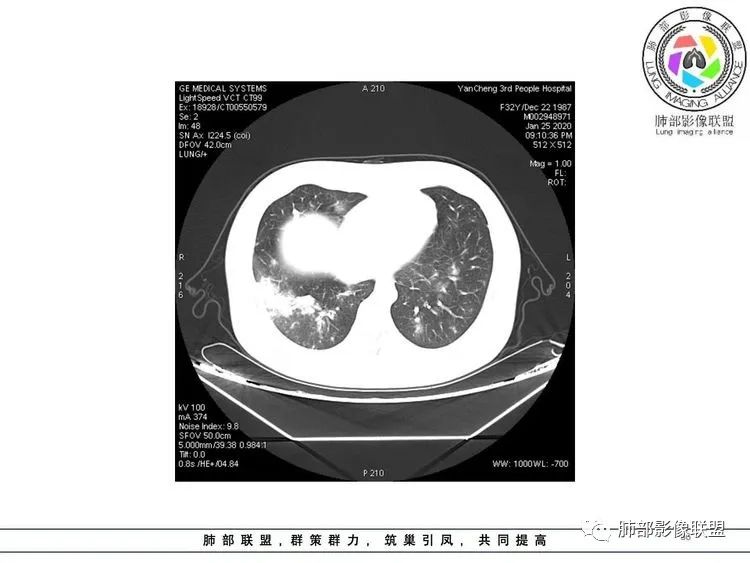

双肺多发大小不等结节,密度不均,右肺中叶及下叶可见大片状实变,中叶支气管壁增厚管腔扩张,考虑感染性病变,结核?

青年女性,发热咳嗽3天,急性病程,化验白细胞不高,双肺散在大小不等高密度结节影,胸膜下也有,右肺中叶及双肺下叶见斑片状高另密度影及实变密度影,首先考虑感染性病变,结核可能大

双肺小叶间隔增厚,双肺多发大小不等的结节,部分结节边缘见晕征,双肺野内见散在分布的斑片状及片状实变影,支气管管壁增厚,考虑感染性病变,病原体不知道。结核不符合(非三均匀),IPA(有无免疫下降病史?),支原体(范围这么广?),NCP(不符合)

双肺多发随机分布点状,斑片状影,以外带及胸膜下分布为主,部分病灶边缘模糊可见晕征,右肺中叶,下叶可见片状实变影,边缘见磨玻璃影,密度不均,可见支气管通气像。考虑感染性病变。真菌?结核?新冠待排。 医学百科网 | YxBaike.Com

两肺多发大小不等结节,部分结节边缘清晰,部分模糊呈小叶核心分布,两肺多发斑片状影,以右肺中下叶为著,下叶病灶部分沿胸膜分布,部分磨玻璃影,部分沿支气管束走行,两肺多发小结节,年轻女性,首先考虑结核,转移待排;合并两肺感染(支原体?病毒?)

青年女性,发热咳嗽3天,急性病程,双肺散在大小不等高密度结节影,右肺中叶及双肺下叶见斑片状高密度影及实变密度影,首先考虑结核可能,结节周围有磨玻璃渗出,需鉴别血管炎。 医学百科网 | YxBaike.Com

青年女性,发热咳嗽三天。双肺弥漫结节、斑片影,周围伴GGO,边缘模糊,胸膜下分布为主,未见明显树芽征。考虑感染性病变,隐球?结核? 医学百科网 | YxBaike.Com

2.双肺多发斑片影及结节影,部分密度较淡为磨玻璃。部分微小结节影高密度且边界清楚。 医学百科网 | YxBaike.Com

病灶分布不符合常见的细菌感染。 医学百科网 | YxBaike.Com